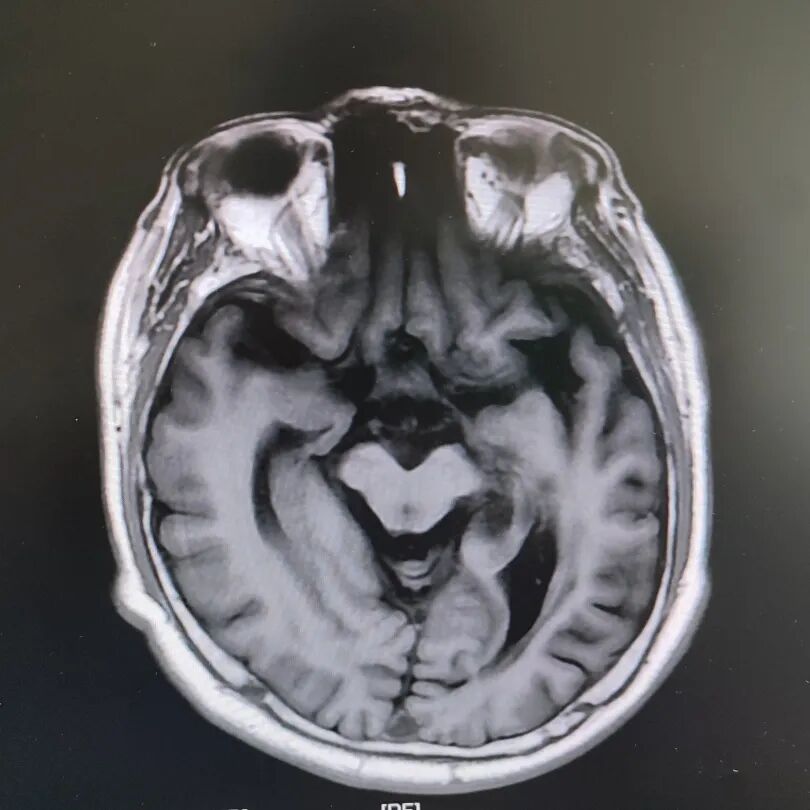

病房里还有另一位患者,来的时候情况更让人揪心:反应迟钝,表情呆滞,行动缓慢。头颅核磁显示脑萎缩明显,但查体发现肌张力、计算力、记忆力、定向力均正常,不符合典型血管性痴呆或阿尔茨海默病表现。

患者头部磁共振影像

凭着多年诊治疑难杂症的丰富经验,赵主任敏锐地意识到这“痴呆”可能是假象,背后另有隐情。他果断建议进一步做特殊感染筛查。果然,检查证实这位患者同样是感染了苍白密螺旋体!经过精准的抗感染治疗,奇迹发生了:患者的反应变快了,眼神灵活了,走路也恢复了正常步态。最终的诊断是“麻痹性痴呆”——一种由神经梅毒引起的、可治疗逆转的“痴呆”类型!